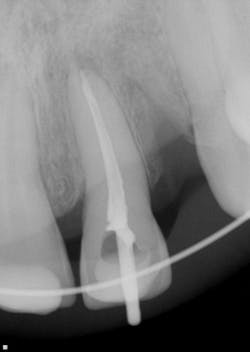

Clinical and radiographic assessment revealed the following (figure 1):

- Complete loss of tooth No. 10 (the patient did not know where the tooth went upon impact).

- Significant swelling in the maxillary and mandibular labial areas with bruising and slight lacerations on the lip and tongue, which were caused when the lower teeth impacted the maxillary teeth with the tongue in between.

- A significant lingual laceration of papilla interproximal to Nos. 8 and 9 with possible involvement of the incisive nerve. Bone exposure was evident.

- Partially avulsed and lingually displaced tooth No. 9 with Class 4 mobility. There was tissue retention only (very light and unstable).

- All other teeth mesial and distal to No. 9 appeared secure.

- Radiographic assessment revealed a horizontal fracture of the alveolar interproximal bone between Nos. 9 and 10 at the apical one-third area. Tooth No. 9 was separated from the alveolar bone with partial avulsion. It was unclear whether the root tip was fractured.

- The patient was unable to bite down due to the mobility and lingual position of No. 9.

Figure 1